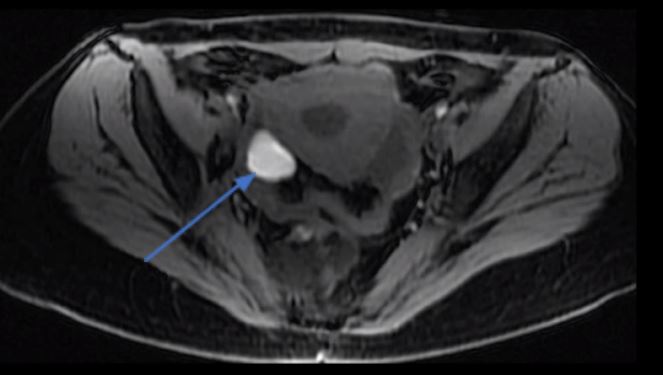

A ressonância magnética da pelve é um método excelente para avaliação dos endometriomas, com sensibilidade e especificidade acima de 95%. Um radiologista experiente consegue diagnosticar corretamente a maior parte dos endometriomas maiores que 1 cm.

Erros de interpretação são infrequentes, mas podem acontecer, especialmente na diferenciação entre um corpo lúteo (cisto de ovulação) e um endometrioma, pois ambos apresentam um conteúdo composto de sangue.

O conteúdo do endometrioma é um sangramento mais antigo e a hemoglobina presente no interior do cisto está mais degradada, gerando um sinal um pouco diferente do endometrioma em uma das sequências na ressonância magnética.

Ressonância magnética para endometriose demonstrando um endometrioma no ovário direito (seta azul).